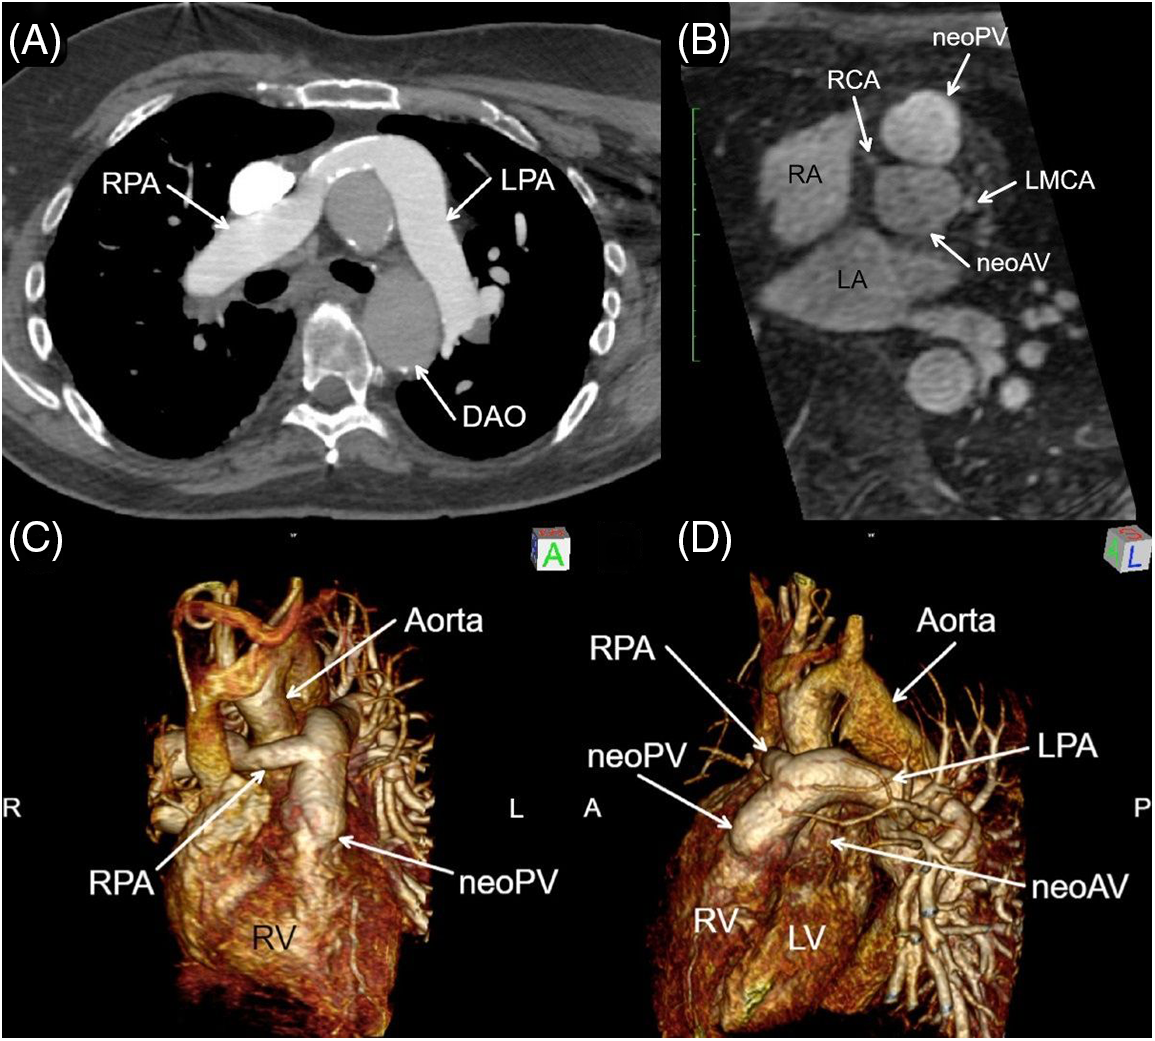

Cardiac magnetic resonance imaging (MRI) and chest computed tomography angiogram (CTA) were performed (Fig. 1). A diagnostic cardiac catheterization demonstrated severe pulmonary hypertension with a pulmonary vascular resistance of 20.2 Wood Units·m2 which decreased to 8 Wood Units·m2 while on epoprostenol and oxygen. He was started on diuretics and phosphodiesterase-5 inhibitor therapy. He did not tolerate endothelin receptor antagonist therapy because of fluid retention. He had a 6-min walk distance of 371 m. He was found to have restrictive lung disease by pulmonary function testing. In addition, he had obstructive sleep apnea and started on continuous positive airway pressure at night.

Figure 1: Axial CTA (A), bi-orthogonal en face neo-aortic valve (neoAV) view chest magnetic resonance angiogram (MRA) (B), and MRA 3D Reconstruction (C, D). Panels A, C, D: The proximal right pulmonary artery (RPA) is a surgical graft, which drapes anterior to aorta consistent with a form of the Le Compte maneuver. Panel B: The neo-pulmonary valve (neoPV) arises directly anterior and rightward to the neoAV, indicative of the pre-surgical anatomic relationship of the semilunar valves in D-transposition of great arteries. Anterior origins of the re-implanted right (RCA) and left main coronary artery (LMCA) are visible. RPA = Right pulmonary artery; LPA = left pulmonary artery; LV = left ventricle; RV = right ventricle; DAO = descending aorta

Based on clinical and imaging data, our patient appeared to have had an early form of an arterial switch operation performed in the mid-1960s. Cardiac MRI demonstrated a form of the Le Compte maneuver with the branch pulmonary arteries draped anteriorly over the aorta. The right pulmonary artery is a surgical graft which did not course under the aortic arch as in Jatenes’s original description. No ventricular septal defect patch was identified, calling into question how the LV remained conditioned prior to his definitive repair. Perhaps, he had a patent ductus arteriosus from birth, which kept LV volume and pressure loaded, but this cannot be confirmed. The direct anterior and rightward relationship of the neo-pulmonary valve to the neo-aortic valve supports the conclusion the preoperative anatomy was d-TGA. The neo-aortic valve is functionally bicuspid and has demonstrated remarkable longevity and durability.

The coronary arteries appeared widely patent with an anterior orientation from the aorta, as is commonly seen following arterial switch operation. There was mild residual right pulmonary artery stenosis. He had significant pulmonary artery hypertension due to pulmonary vascular obstructive disease, which likely occurred since the pulmonary vascular bed was not well protected early in life. The pulmonary artery hypertension was responsive to epoprostenol and oxygen and is currently managed on tadalafil. There was some evidence of LV diastolic dysfunction that required diuretic therapy. According to the 2018 American Heart Association/American College of Cardiology Guideline for the Management of ACHD, he is ACHD AP Class IIIC [8]. He was followed by our ACHD service but recently moved abroad and has since been lost to follow-up.